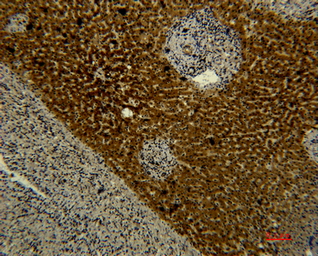

IHC-P analysis of rat liver tissue using GTX34267 Transferrin antibody [5F9].

Dilution : 1:50

IHC-P analysis of human liver tissue using GTX34267 Transferrin antibody [5F9].